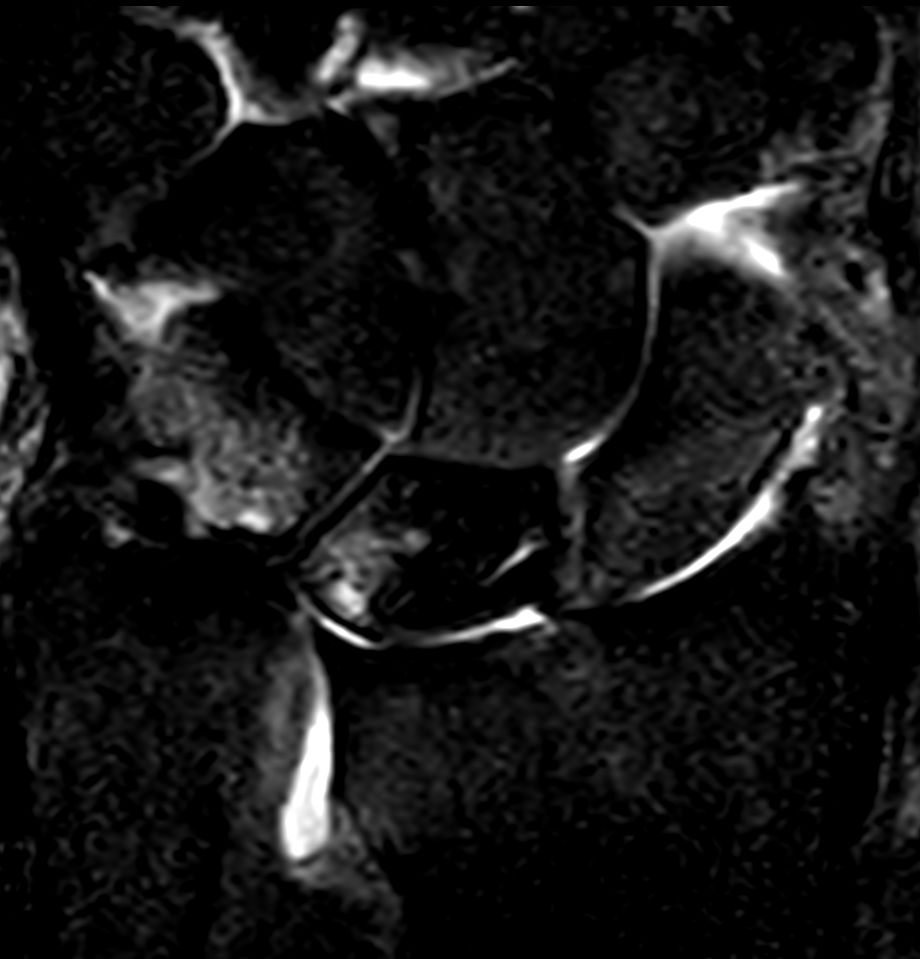

Patient with a lesion in his wrist. dS Microscopy coil set is used, consisting of two 47 mm coils, for small field-of-view imaging with high in-slice spatial resolution and a high signal-to-noise ratio. Compressed SENSE is used in all sequences to shorten the overall exam time for the patient.

Coronal T2w TSECompressed SENSE